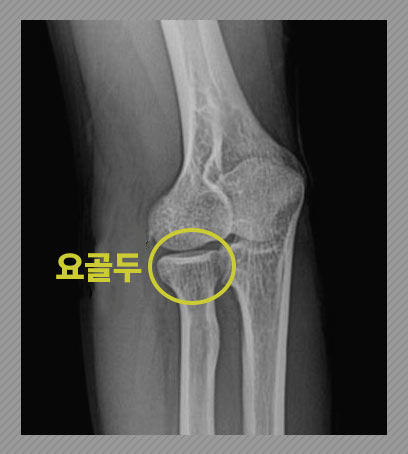

주관절 요골두 골절

모든 팔꿈치 골절의 약 30%가 요골두에서 나타난다고 하는데요. 그 위치는 다음과 같습니다.

대부분 손을 뻗은 상태로 넘어지면서 골절, 탈구가 발생합니다. 뼈가 원래 위치에서 어긋나지 않은 비전위이거나 전위가 심하지 않다면 깁스 등 보존적 치료가 가능합니다. 하지만 전위가 심한 경우 또는 골절편이 여러 개인 분쇄 형태라면 수술적 치료가 필요할 수 있습니다. (내고정술, 절제술, 인공관절 치환술 등)